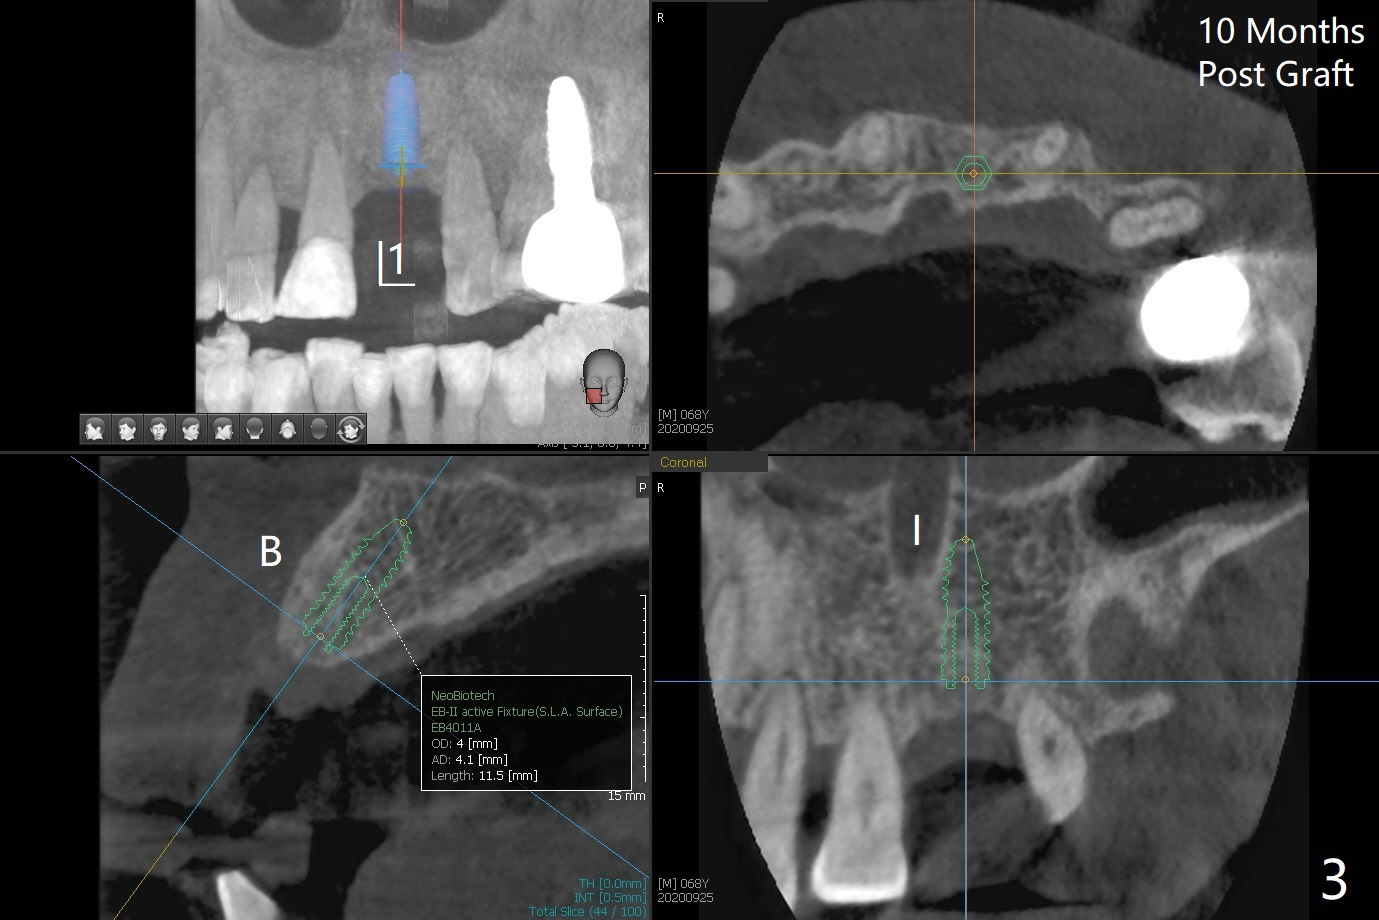

左上1(图一)拔除,植骨,使用带钛架不可吸收膜(图二)后十个月准备植牙(图三),在没有术中根尖片指导下(导板习惯),在牙槽嵴正中开始钻洞,第一个钻头最后一两个毫米觉得有突破感,但是颊侧舌侧没有穿孔,然后植入3.5x11.5毫米植体(图五,扭力>35 Ncm),术后射线表明植体接近切牙管(图四:*)。考虑到病人要离城,颊侧第一螺纹暴露(图六),舌侧骨板薄(图五),植骨,放置愈合基台(图七)。 术后十一天CT显示植体没有侵犯切牙管(图八:I);植体颊侧骨粉(箭头)似乎可以解释颊侧饱满(图九)。第二原因是减张缝合,胶原膜暴露(*),而下面骨粉没有暴露,以后伤口应该是二期愈合。